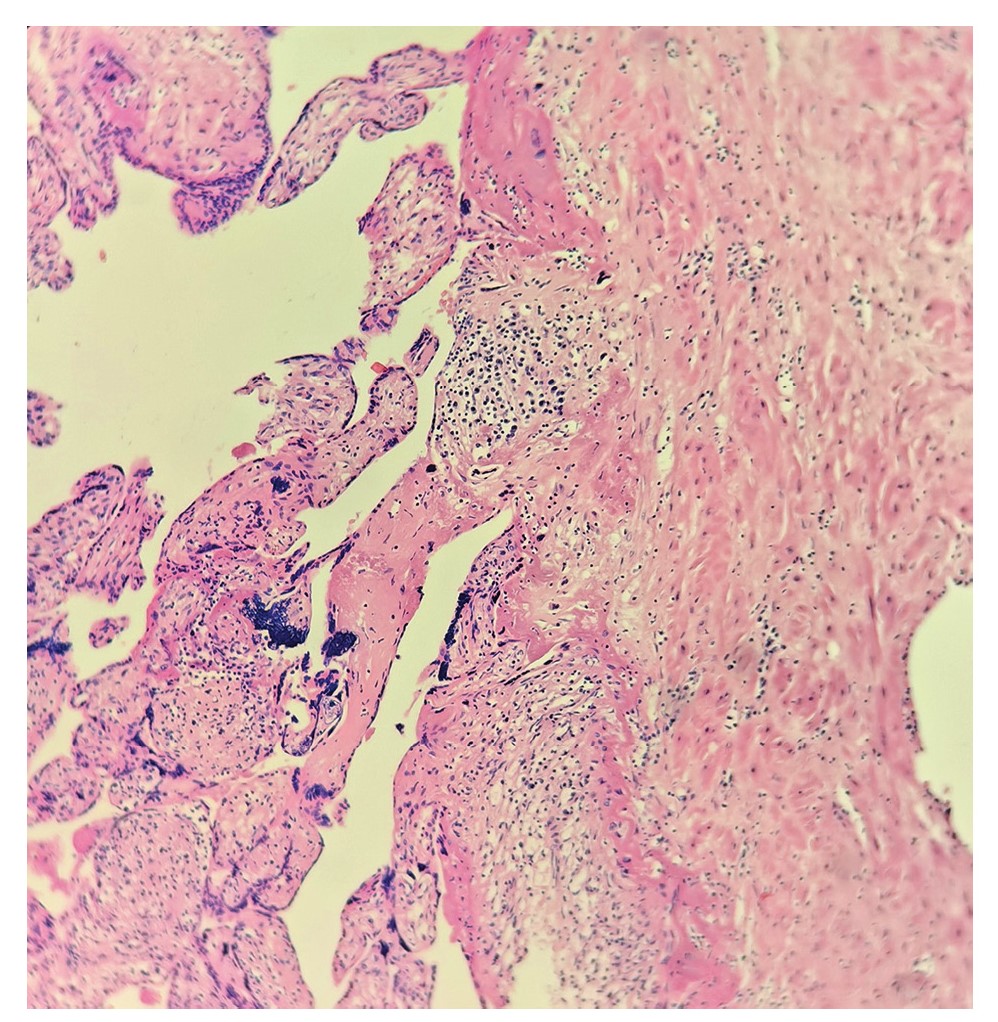

Гистологическое заключение по матке: в области патологической имплантации определяется широкая зона фибриноидного некроза с вовлечением сосудов и мышечной ткани, плацентарная ткань в большом количестве пенетрирует мышечные волокна, подрастая на отдельных участках к эндометрию, часть ворсин замурована в большое количество фибрина (рис. 5). Перифокально отмечается лимфоидно-лейкоцитарная реактивная инфильтрация, кровоизлияния. Эндометрий с десквамацией, железы и строма с неполноценной гравидарной трансформацией, очаговой лимфоидно-лейкоцитарной инфильтрацией. Мышечные волокна миометрия неравномерно гипертрофированы, с умеренно выраженными дистрофическими изменениями миоцитов и резко выраженным интерстициальным отеком, разрастанием соединительной ткани между волокнами. Сосуды с утолщенной фиброзированной стенкой. Серозная оболочка отечная, с мелкоочаговыми кровоизлияниями. Патоморфологический диагноз: ЭБ (34+4 нед гестации по клиническим данным) с локализацией в БП, имплантацией в области дна и правого угла матки, гистопатические изменения миометрия.

Рис. 5. Микропрепарат: место имплантации (окраска гематоксилин-эозином, ×250).

Fig. 5. Slide: implantation site (hematoxylin-eosin stain, ×250).